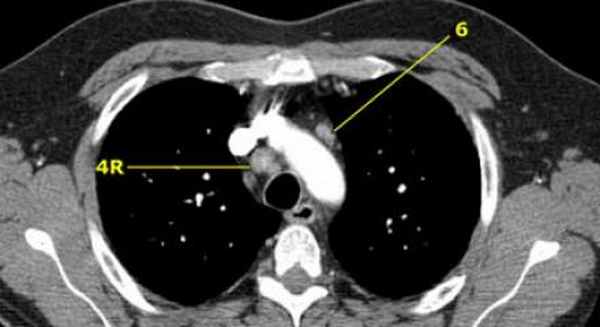

4R. Правые нижние паратрахеальные лимфатические узлы

Верхняя граница: пересечение нижнего края левой плечеголовной вены с трахеей.

Нижняя граница: нижний края непарной вены.

4R узлы распространяются до левого края трахеи.

На изображении слева мы видим 4R паратрахеальные узлы. Кроме того здесь представлен узел кнаружи от дуги аорты, то есть 6 группы.

6. Парааортальные лимфатические узлы

Парааортальные лимфатические узлы лежат кпереди и кнаружи от восходящего отдела аорты и между верхним и нижним краями дуги аорты.